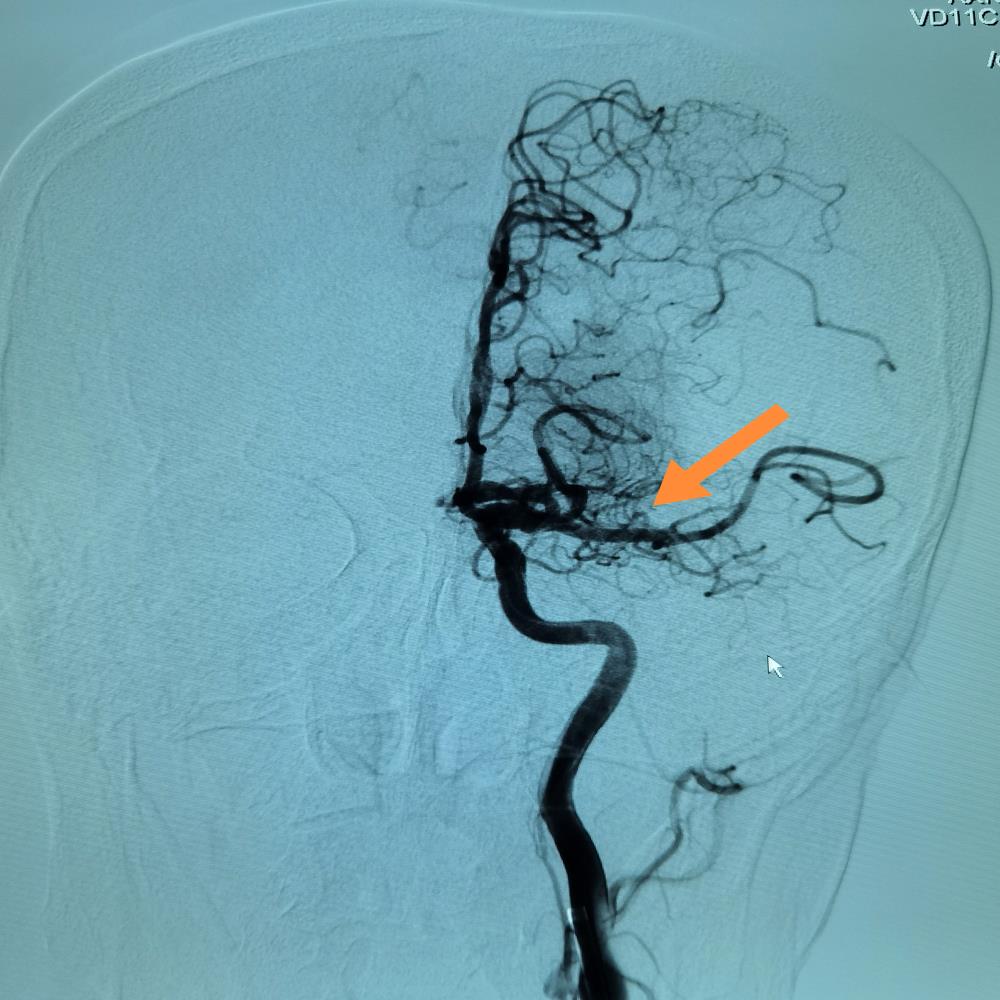

在卒中中心诊查后,急行头颅影像检查,发现该患者大面积脑梗死,左侧大脑中动脉闭塞,病情危重,收住脑科医院神经内科一病区。

根据患者的病史和既往史,考虑其脑梗死为心源性栓塞型,NIHSS评分达18分,急查凝血INR大于1.7。脑科医院常务副院长王晓成主任医师根据患者的病情做出指示,给予患者介入手术开通颅内闭塞血管,李雪医生团队迅速为患者进行介入手术取栓治疗,手术顺利,血管完全再通。

术后,经过脑科医院神经内科一病区医护人员对患者精心的治疗,患者病情明显好转,出院时NIHSS评分2分。